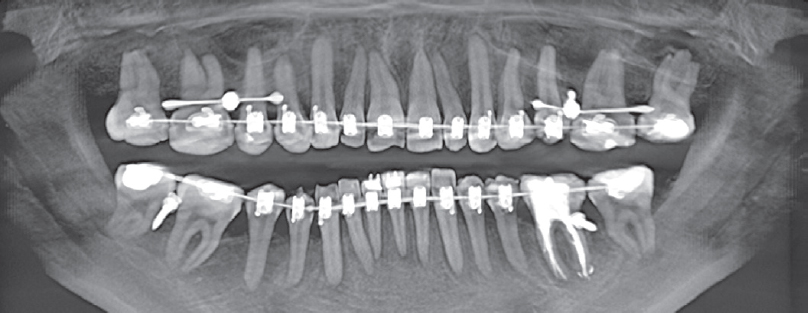

Computed tomography (CT) of the jaws, lateral cephalometric radiographs, TMJ CT, and functional diagnostic tests were performed (Figs. 4–6).

Fig. 5. Section of computed tomography of the jaws before treatment.

Рис. 5. Срез компьютерной томограммы челюстей до лечения.

Orthodontic microimplants were then placed in FDI quadrants 1 and 2 for occlusal plane correction (Figs. 15, 16).

Fig. 16. Section of computed tomography of jaws after nano-osteoperforations.

Рис. 16. Срез компьютерной томограммы челюстей после нано-остеоперфораций.

The thickness of the bone surrounding each tooth was measured before and after nano-osteoperforation (Figs. 17, 18).

Fig. 17. Sections of computed tomography of the jaws before (a) and after (b) nano-osteoperforations, in the teeth area 1.4–2.4.

Рис. 17. Срезы компьютерной томограммы челюстей до (a) и после (b) нано-остеоперфораций, в области зубов 1.4–2.4.

Fig. 18. Sections of computed tomography of the jaws before (a) and after (b) nano-osteoperforations, in the 4.4–3.4 teeth region.

Рис. 18. Срезы компьютерной томограммы челюстей до (a) после (b) нано-остеоперфораций, в области зубов 4.4–3.4.

In the majority of cases, the thickness of the cortical plate was lower than that of the trabecular bone. Nano-osteoperforations typically result in a decrease in both cortical and trabecular bone thickness, reducing the duration of orthodontic treatment. Bone thickness variations between teeth indicate heterogeneity of the surrounding bone tissue structure.